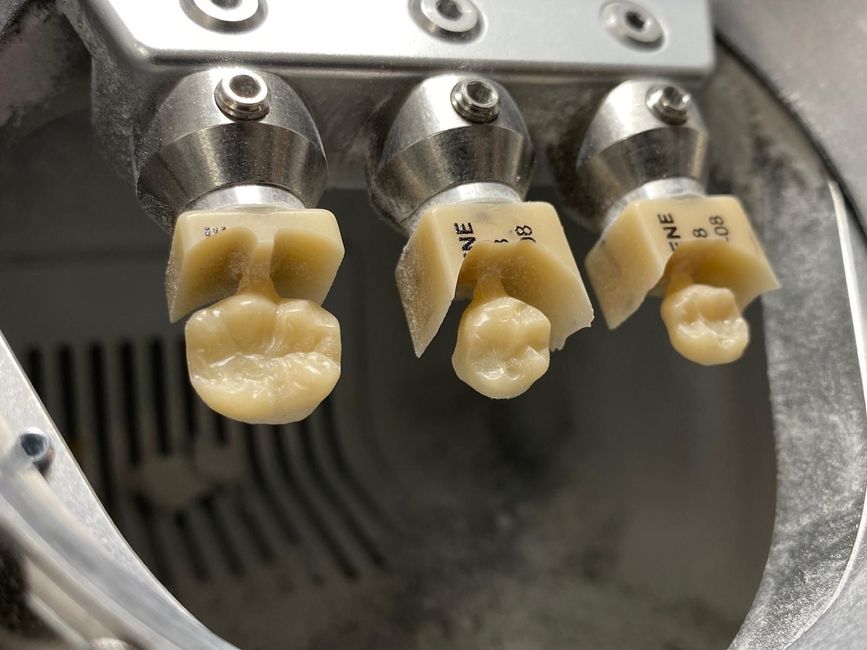

GALERIA DE TRABAJOS